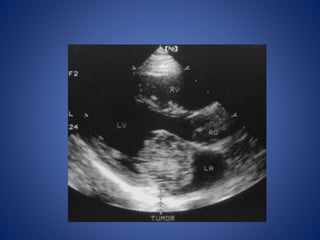

Cardiac diseases

• Cardiac disorders are the most common cause of ischemic stroke

in children and account for up to 50% of strokes.

• The risk of stroke in children with congenital heart disease is

related to the abnormality, diagnostic and surgical procedures,

and associated genetic or acquired factors that predispose

children to thrombosis.

• Cardiac disorders can lead to the development of intracardiac

thrombi that may embolize to the brain or can lead to

thrombosis in cyanotic patients with anemia

Cerebral Embolism From Atrial Myxoma in Pediatric Patients. Majeed Al-Mateen, Margaret Hood, Don

Trippel, Samuel J. Insalaco, Randolph K. Otto and Kari J. Vitikainen. Pediatrics 2003;112;e162.